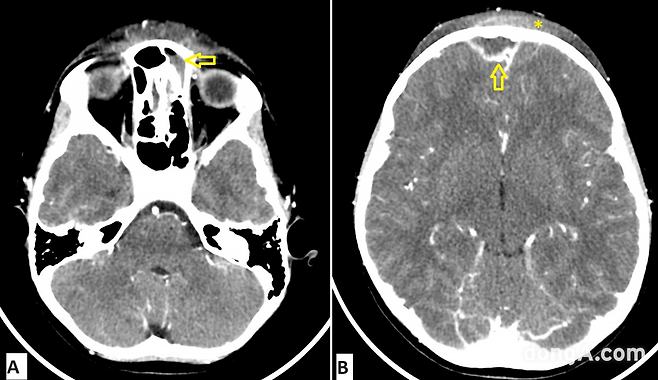

CT 검사 결과, 급성 전두동염(이마 부위 축농증)이 두개골과 그 주변으로 퍼졌다는 사실이 밝혀졌다.

의료진은 뇌와 가까운 부위까지 감염이 퍼지는 희귀 질환인 ‘팟츠 퍼피 종양(Pott’s Puffy Tumor)’을 진단했다.

아이에게는 이마 뼈 속에 고름이 고인 ‘골수염’과 ‘피하 고름집’, ‘두피 염증’까지 나타났다.